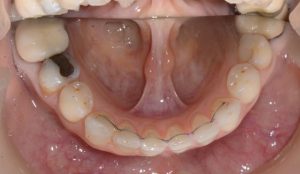

השיוף נעשה לצורך השגת מקום ליישור שיניים צפופות כאשר לא מעוניינים לעקור שיניים.

במקרים בהם ישנה צפיפות גדולה מאוד של שיניים ו /או בליטה גדולה שלהן כלל הטיה אלכסונית שגורמת לליקוי אסתטי יפנה האורתודונט את המתרפא/ה לעקירות שיניים קבועות.